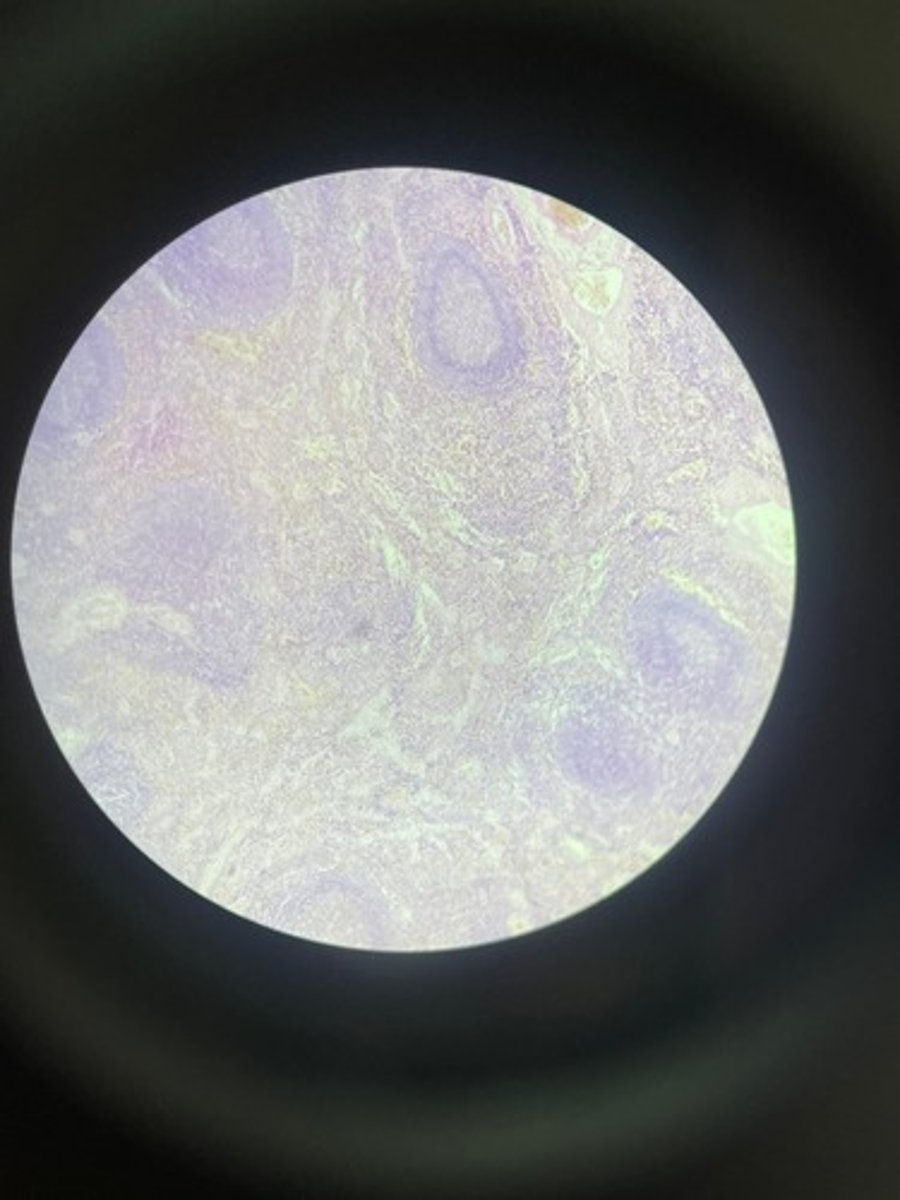

Lymph node HE

Lymph node HE

Lymph node HE

lymph node HE

Lymph node HE

Lymph nodes HE